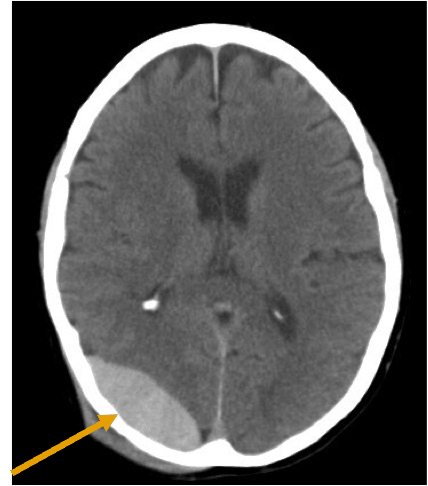

Hematoma epidural: Entre que meninges se forma y manejo quirúrgico Sangrado entre duramadre y calota. Principalmente arterial pero también puede ser venoso. Manejo QUIRURGICO: Vol >30ml, coágulo >15mm, desviación de linea media de >5mm.

Hematoma subdural: Entre que meninges se forma y manejo quirúrgico Sangrado entre duramadre y aracnoides. Sangrado venoso. Quirúrgico SI: Desviación de linea media >5 mm o grosor mas de 10 mm.